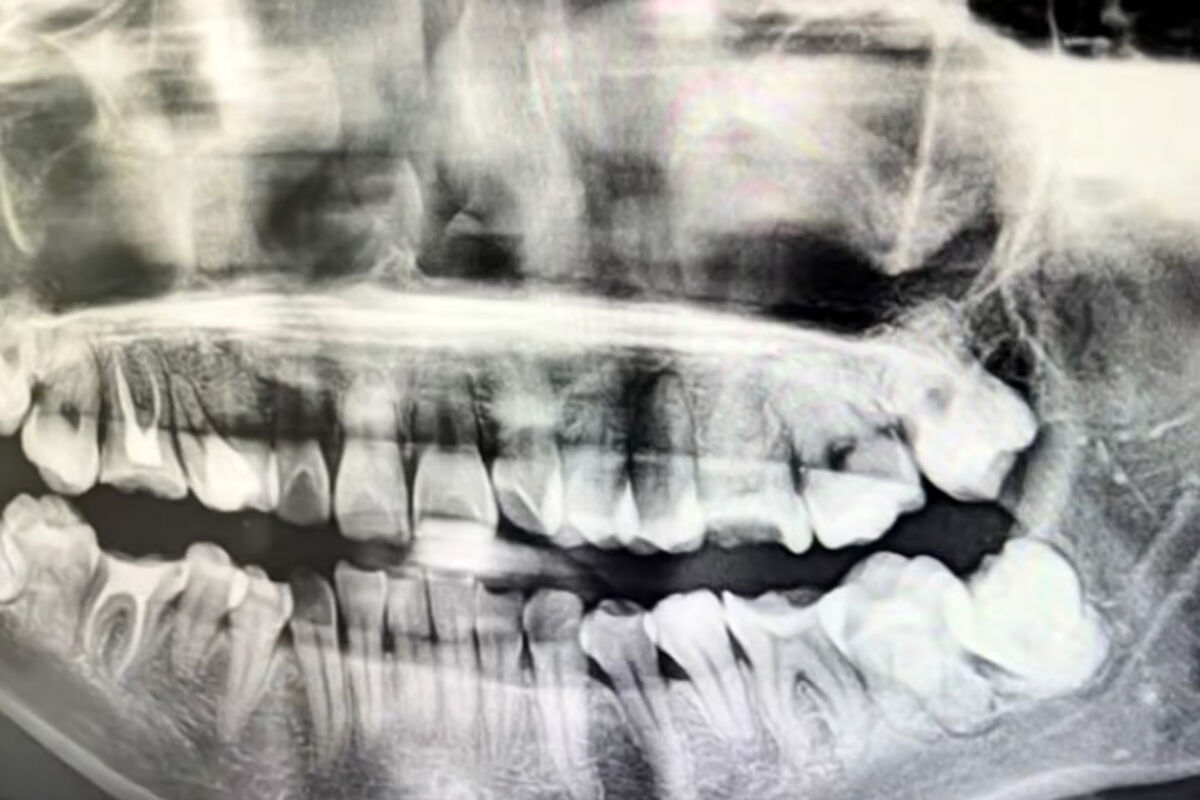

Истончение кости вокруг зубного импланта чаще всего происходит из-за естественного снижения нагрузки на костную ткань, инфекций и неправильного выбора изделия. Курение и сахарный диабет дополнительно повышают риск. Об этом «Газете.Ru» рассказал кандидат медицинских наук, врач-стоматолог-имплантолог Игорь Кузьмин.

«Одна из причин — биомеханика. Имплант не имеет естественной связки зуба, которая амортизирует нагрузку. Жесткий титановый корень забирает на себя давление при жевании, а кость вокруг получает меньше стимулов, что может приводить к ее истончению», – пояснил специалист.

Обратная ситуация — чрезмерная нагрузка на имплант, например при бруксизме или неправильно установленной коронке, тоже провоцирует разрушение кости.

«Инфекции — еще один фактор. Воспаление десны вокруг импланта (мукозит) может перейти на кость (периимплантит). Бактерии активируют клетки, разрушающие кость, что часто происходит быстрее, чем при заболеваниях собственных зубов. Курение и сахарный диабет дополнительно увеличивают риск», – предупредил врач.

Стоматолог добавил, что гладкая эмаль зуба легче очищается, а шероховатая поверхность импланта является идеальным плацдармом для бактерий, если гигиена нарушена.

Стоматолог добавил, что даже конструктивные особенности импланта влияют на здоровье кости. Микрозазоры между ним и абатментом (опорой) могут стать «входом» для бактерий, поэтому современные системы стараются сделать соединение герметичным. Быстрая и надежная остеоинтеграция — срастание кости с имплантатом — также снижает риск истончения.

К другим причинам истончения кости относятся перегрев при формировании ложа для импланта (некроз кости), неправильный выбор размера или позиции имплантата, а также некачественную фиксацию коронки, когда цемент выдавливается в десну и вызывает хроническое воспаление.